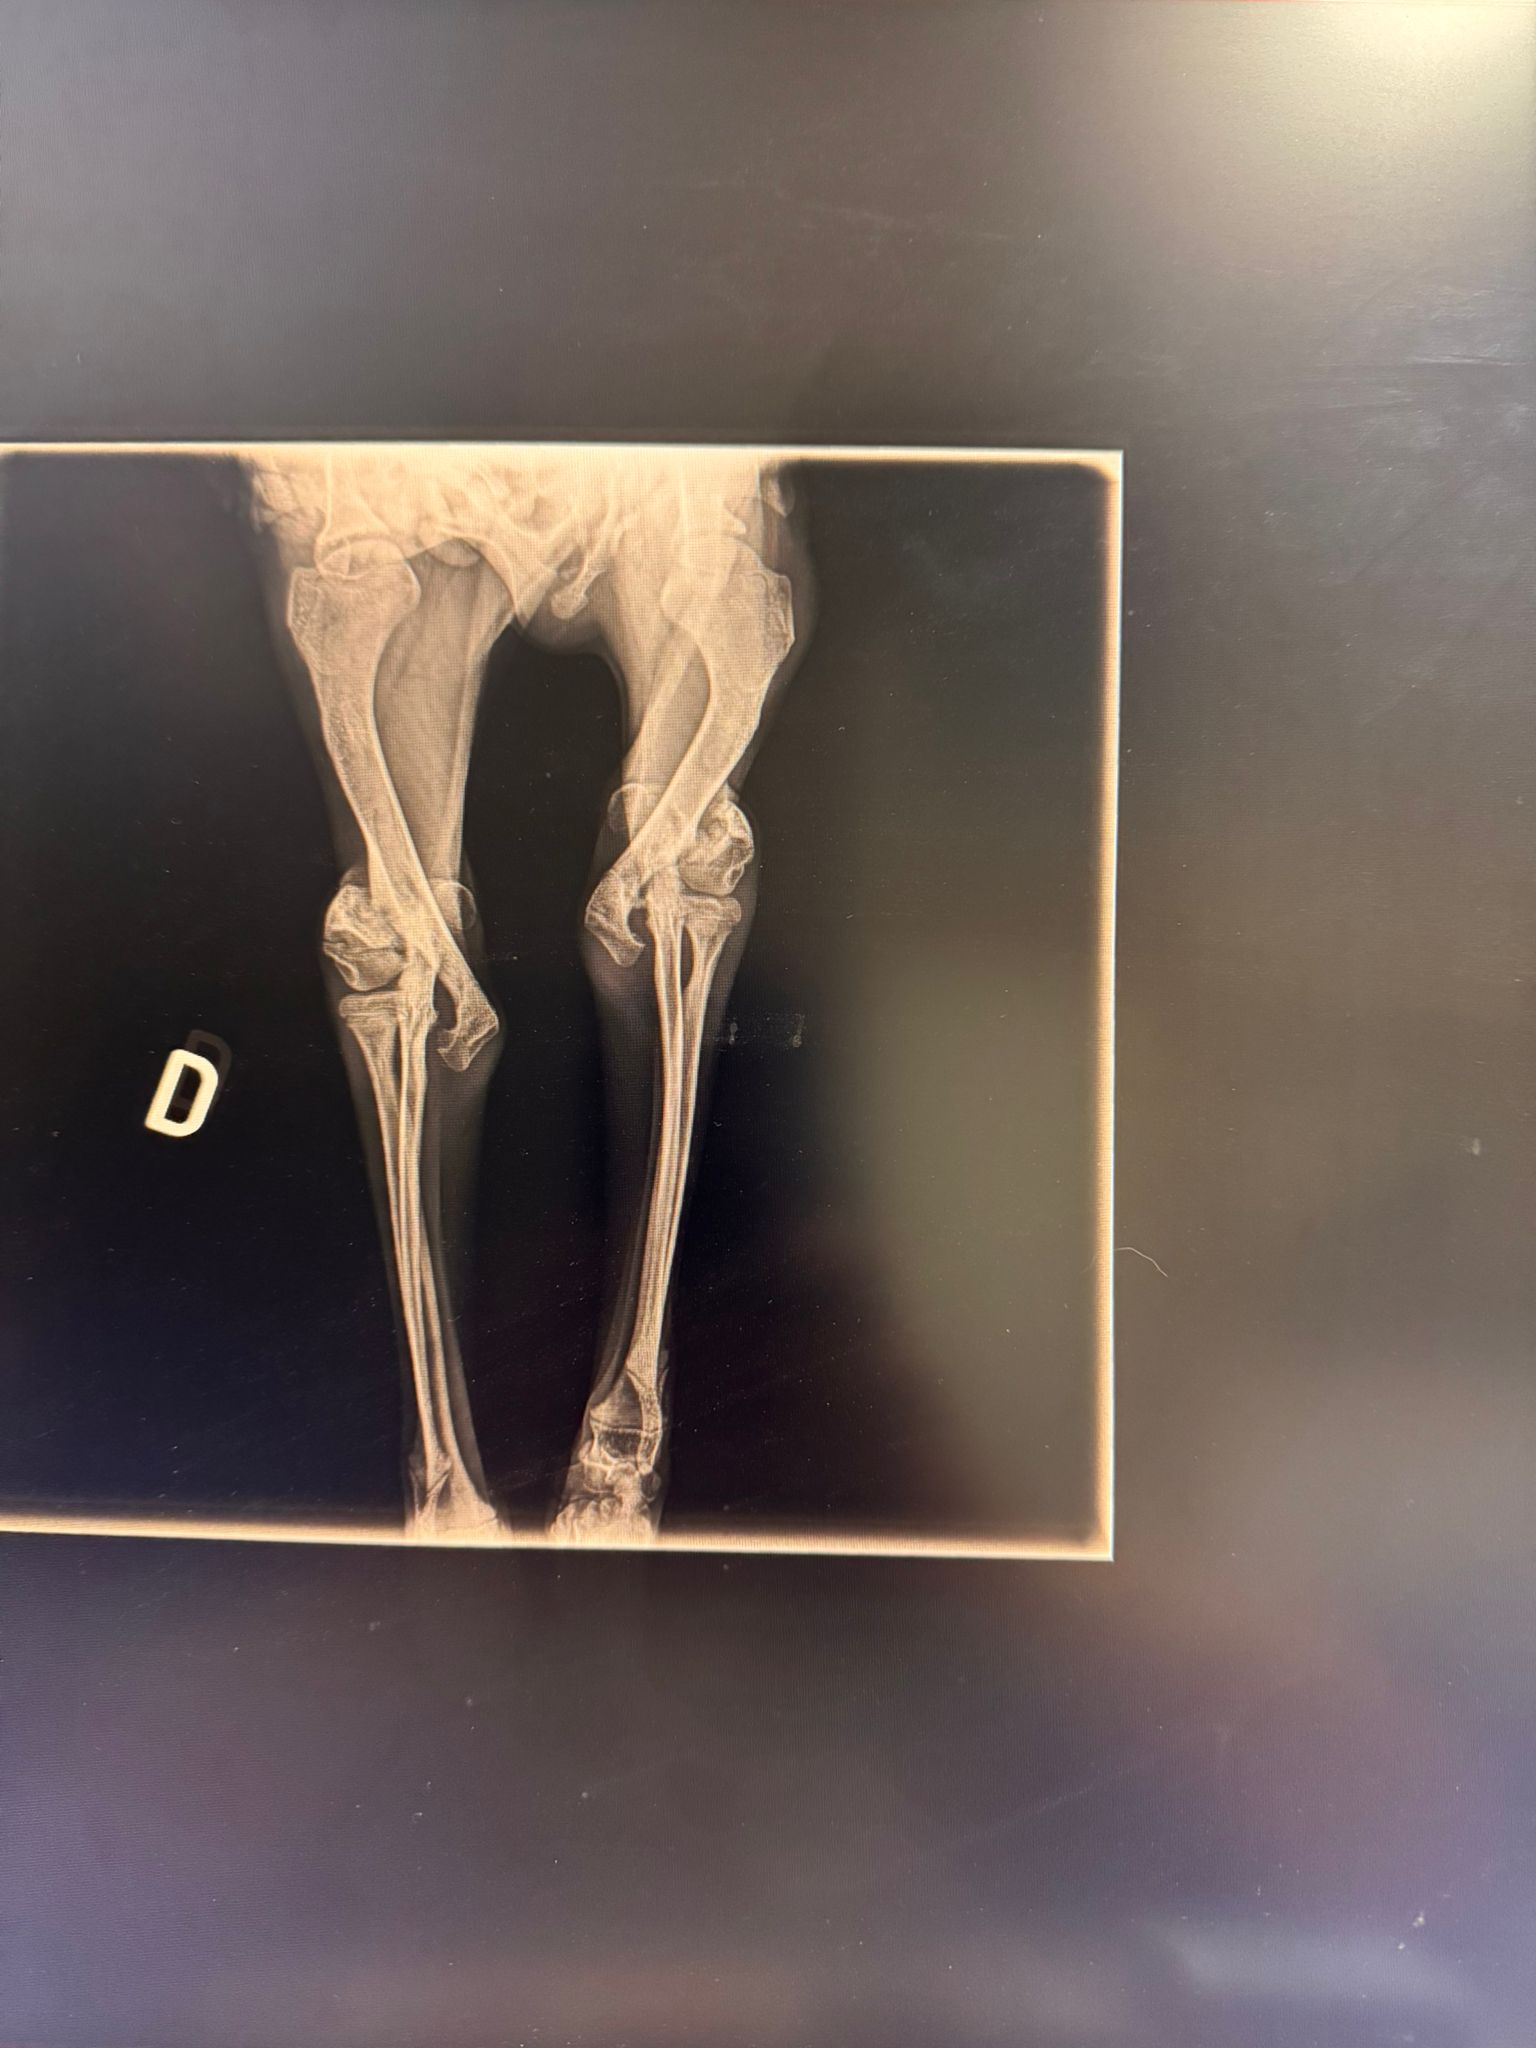

Fractura bilateral de cóndilo lateral, Salter-Harris tipo 4

Y es que Cancho ha sufrido un fuerte traumatismo siendo muy bebé; esto suele pasar cuando caes de una altura considerable. Sus dueños decidieron abandonarlo, la perrera lo recogió y de ahí nos llamaron. Os prometemos que hemos corrido todo lo posible, pero esta vez hemos llegado tarde; no sabemos cuándo fue este golpazo, pero lo que sí sabemos es que ha pasado demasiado tiempo como para poder reparar sus fracturas.

Hoy, durante la cirugía, los pequeños huesos estaban destrozados y llenitos de artrosis. Y no, esta vez tenemos que contaros que no hay reparación posible y que nuestro chico guapo deberá aprender a caminar así.